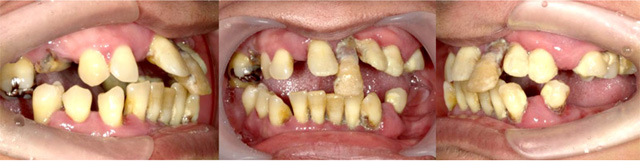

そこで、誕生したのが、

ボロボロの歯の状態を1回目の治療で、歯の痛みや腫れだけでなく、歯の大きさ、色、形、歯並びまでをすべてきれいにし、最短2回で自然な状態にする”カスタムセラミック法”という治療です。

どんなボロボロの歯にも対応 私たちは、ボロボロの歯の方の治療を得意にしているために、通常の虫歯ではない、何年も放置されたどんなボロボロの歯でも、対応することができます。 |

1回目の治療で痛みも見た目がきれいに 私たちは、1回目の集中治療によりすべての虫歯を治療した後で、白いきれいな仮歯(プラスチック製)をかぶせるので、初回来院時に、痛みも見た目もきれいな口元になります。 |

時間がない方の向けの短期治療 2回目に、前回かぶせた仮歯をセラミックの歯に取り替えて、自然な歯の状態になります。最短2回で、治療完了となります。 |

オールオン4の治療例:1

治療前

治療後

オールオン4の治療例:2

その他 ボロボロ虫歯の症例